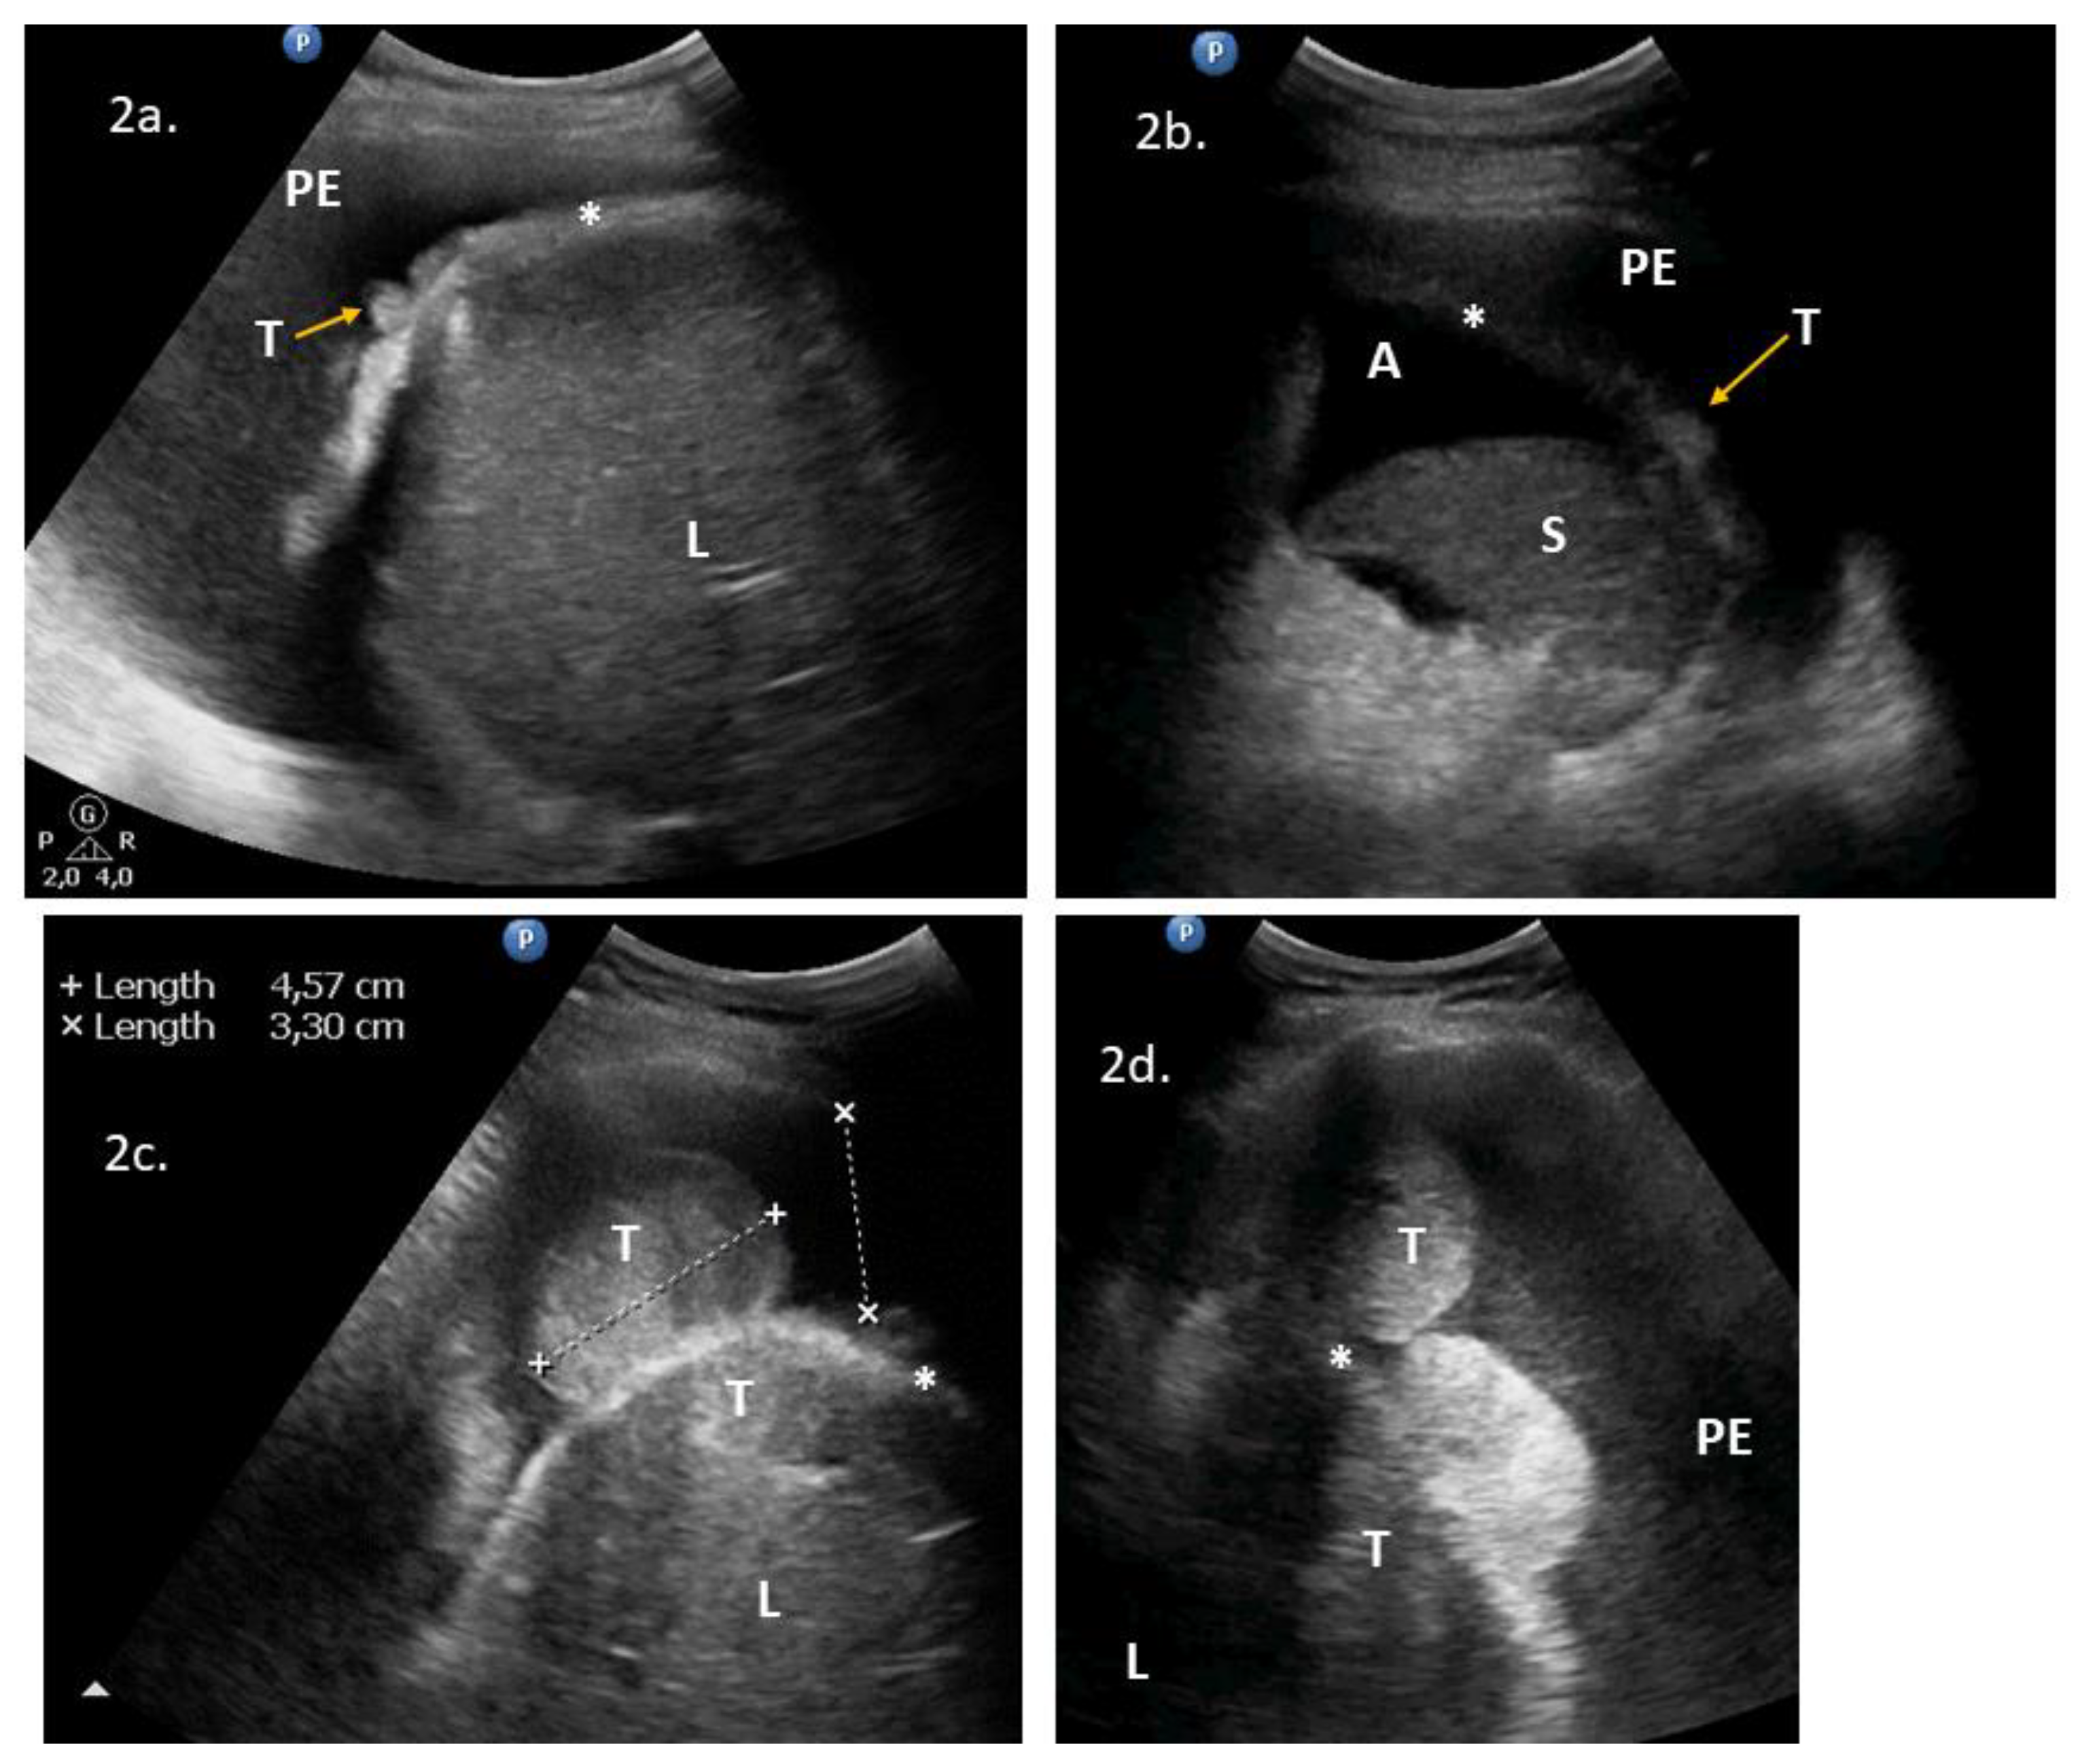

| 1 | 71 | 3 | ascites, massive pelvic involvement, omental involvement, spleen involvement | pleural diaphragm involvement *, pleural effusions | ascites, carcinomatosis, massive pelvic involvement, omental involvement, pleural effusions, spleen involvement | Yes | Yes | NoScore: 9 → 11 High → High | Could replace DLSK | 2a | DLSK, HGSOC, NACT |

| 2 | 62 | 1 | ascites, carcinomatosis, omental involvement, spleen involvement | abdominal diaphragm involvement **, pleural effusions, ligamentum teres of the liver involvement | - | Yes | Yes | YesScore: 6 → 8 Intermediate → High | Could precede PDS | 2b, VS1 | PDS attempt. HGSOC, R > 1 cm |

| 3 | 53 | 3 | ascites, massive pelvic involvement, omental involvement | abdominal diaphragm involvement **, pleural diaphragm involvement *, pleural effusions | - | Yes | Yes | YesScore: 6 → 8 Intermediate → High | No | 2c, 2d, 3a, VS2 | PDS, mucinous G3. R = microscopic |